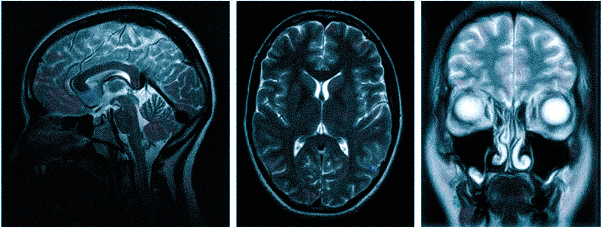

МРТ при головных болях (в трех проекциях): специальная программа выстраивает объемные изображения полученных срезов, что позволяет увидеть даже мельчайшие изменения и отдифференцировать патологию от нормы

Причин головной боли множество, и их не всегда возможно определить без помощи современных способов визуализации. Цефалгию вызывают: повышенное внутричерепное давление, сосудистые мальформации, опухолевые процессы, постравматические осложнения. Какую МРТ делать при головной боли или предпочтительней пройти КТ — зависит от предполагаемого характера патологии. Все методы являются взаимодополняющими, но что лучше в конкретном случае, выбирает врач с учетом жалоб, показаний и противопоказаний. МРТ и КТ с контрастным усилением позволяют получить сопоставимые по качеству снимки, но при этом используют разные принципы построения изображений. Чем раньше будет найдена причина и проведено адекватное лечение, тем больше шансов на полное выздоровление.

Выделяют несколько видов магнитно-резонансной томографии головы: нативную, усиленную контрастным препаратом и сканирование в ангиорежиме. К каждому исследованию есть свои показания, поэтому ответить на вопрос: “Какую МРТ делать при головной боли?” — не всегда возможно. Врач выбирает нужный тип диагностики, опираясь на клиническую картину. В оценке опухолевых новообразований и для определения стадийности (в том числе — метастатического распространения) используют МРТ с контрастированием. Введение препаратов на основе хелатов гадолиния позволяет рассмотреть даже небольшие опухоли в труднодоступных местах, поэтому магнитное сканирование с усилением с успехом применяют, если прочие способы визуализации показали неоднозначные результаты. При подозрении на сосудистое заболевание головного мозга оптимальным выбором будет проведение сканирования в ангиорежиме.